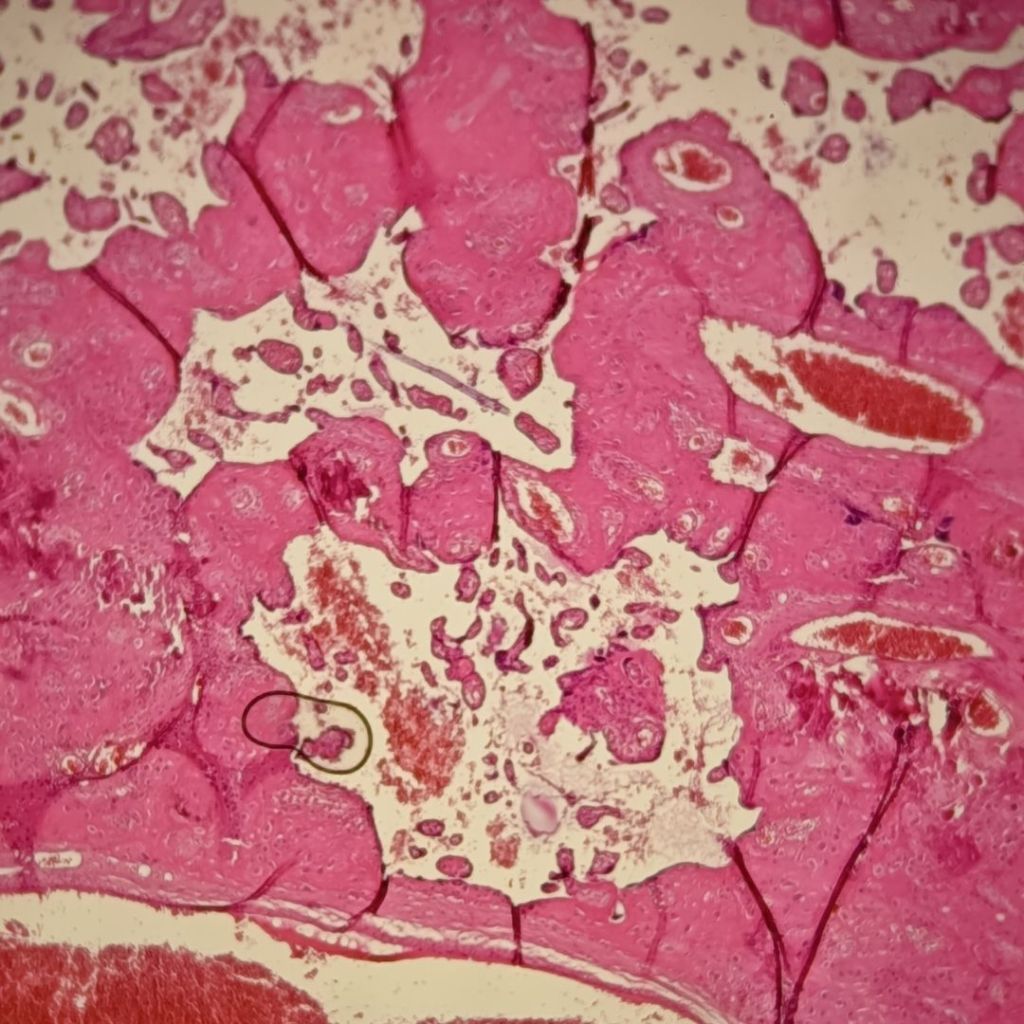

Desde el punto de vista técnico, un artefacto es una estructura que no forma parte del tejido original, pero que aparece en el preparado debido a alguna alteración durante el proceso técnico. El desafío es poder reconocer estas alteraciones y no confundirlas con estructuras normales o lesiones reales, ya que en ciertos casos pueden incluso interferir con el diagnóstico.

Por eso es importante desarrollar el criterio para identificarlos, entender cómo y por qué se producen y, en lo posible, aprender a prevenirlos. En la práctica, pueden observarse artefactos muy comunes (como pliegues, burbujas, roturas), y otros menos frecuentes que también conviene conocer.

Los artefactos pueden surgir en cualquier etapa de la preparación histológica, desde la obtención del tejido hasta el montaje final.